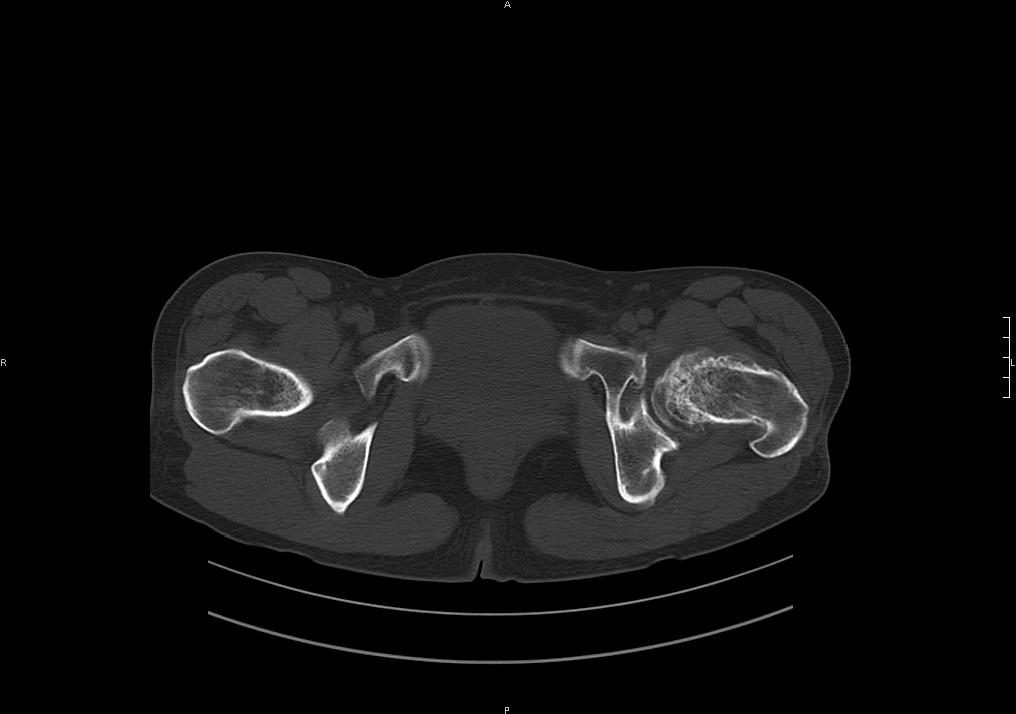

标题: CT19780左髋关节疼痛伴跛行1年,加重1个月。无菌性坏死? [打印本页]

标题: CT19780左髋关节疼痛伴跛行1年,加重1个月。无菌性坏死?

左髋关节内内可见关节鼠及滑囊积液.

考虑为滑膜骨软骨瘤病.

滑膜增厚钙化,关节鼠及滑囊积液,髋臼增生。考虑骨性关节病

髋臼平浅,股骨头覆盖率减小,考虑双侧髋关节发育不良伴退行性变。

股骨颈陈旧性骨折

髋关节退行性骨关节病

滑膜增厚钙化,关节鼠及滑囊积液,髋臼增生。考虑骨性关节病。